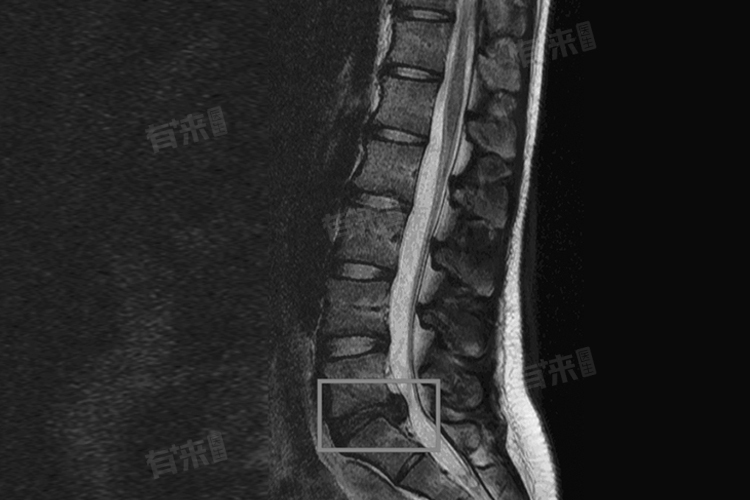

2、中重度腰间盘突出:对于中重度腰间盘突出的患者,针灸治疗虽然也能起到缓解症状的作用,但效果可能相对有限。这是因为中重度腰间盘突出往往伴随着较为严重的神经压迫和炎症反应,单纯的针灸治疗可能无法完全解除压迫和消除炎症。此时针灸可以作为综合治疗的一部分,与药物治疗、物理治疗、牵引治疗等相结合,以提高治疗效果。在病情严重或保守治疗无效的情况下,可能需要考虑手术治疗。